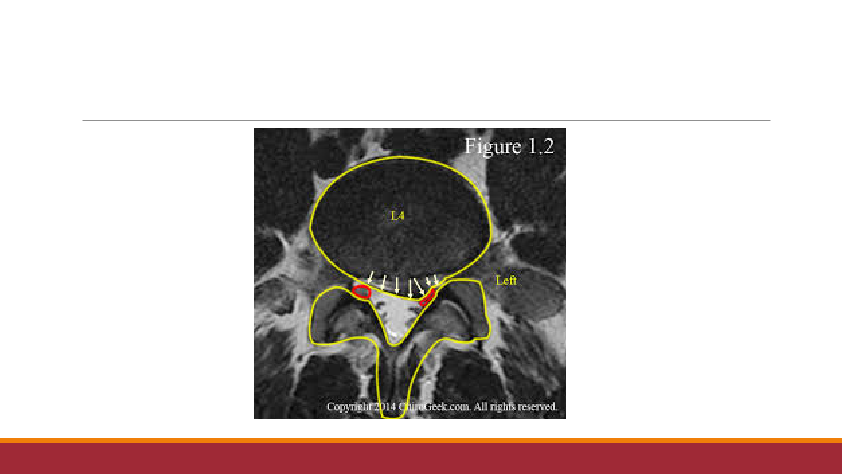

腰椎间盘突出